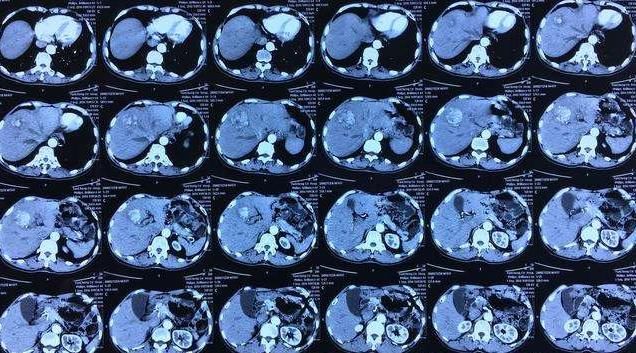

昨天他还非常“健康”,送发烧的妻子到医院输液,医生发现他有明显的黄疸症状,建议他去检查一下肝,结果查出肝区异常占位,甲胎蛋白870ug/L,确诊肝癌晚期。